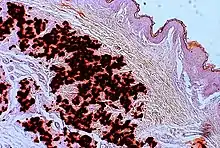

- Diagnostic histopathological changes in lesional skin: Calcified elastic fibers in the mid and lower dermis, confirmed by positive calcium stain

| Pseudoxanthoma elasticum | LM: Mid-dermal calcification and fragmentation of elastic fibers EM: Mineralization in elastic fiber core |

In PXE, there is mineralization (accumulation of calcium and other minerals) and fragmentation of the elastin-containing fibers in connective tissue, but primarily in the midlaminar layer of the dermis, Bruch's membrane and the midsized arteries.[26] Recent studies have confirmed that PXE is a metabolic disease, and that its features arise because metabolites of vitamin K cannot reach peripheral tissues.[27] Low levels of PPi cause mineralization in peripheral tissues.[19]